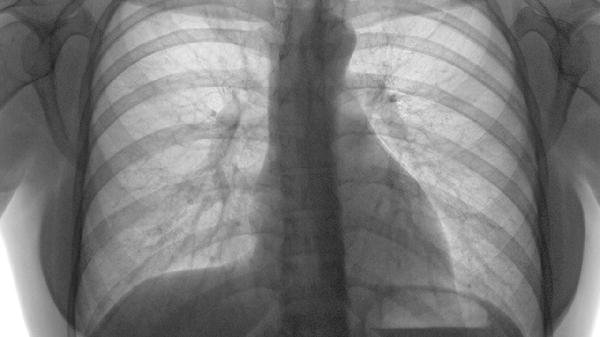

4、肝炎:

肝脏炎症会导致肝包膜牵张引发右季肋区隐痛,病毒性肝炎多见。伴随症状包括乏力、食欲减退、尿色加深,严重时出现黄疸。需检测肝功能与肝炎病毒标志物,保肝治疗常用甘草酸二铵、水飞蓟宾等药物,慢性乙肝需长期抗病毒治疗。